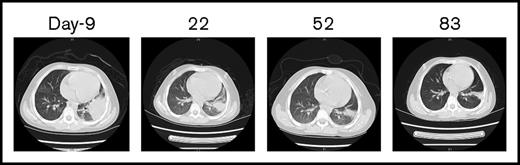

The CBC recovery was accompanied by disappearance of allo–CAR-T cells and increased MRD. Therefore, a second CAR-T course from her own source was initiated. At time of apheresis, the collected cells were 100% of her own based on genotyping, with an absolute lymphocyte count of 0.97 × 109/L and 45% CD3 T cells. Cyclophosphamide 400 mg/m2 and fludarabine 30 mg/m2 conditioning regimen was given on day 51, and autologous CAR-T cells (0.16 x 106/kg) were infused on day 56, which was well tolerated. CAR-T–cell expansion was detected on day 64, and the patient received etanercept for an associated fever. Her temperature returned to normal by day 66. On day 78, 23 days after the auto–CAR-T infusion, BM examination indicated CR by histology and flow cytometry (Figure 2D). Chromosomal analysis showed complete normal phenotype (46, XX) without abnormal clones. Computed tomography (CT) scans of lungs revealed complete resolution from previous infections by day 83 (Figure 3). Because of the lack of matched unrelated donor, and a negative test result for donor specific antibody, the patient subsequently underwent haploidentical hematopoietic stem cell transplantation from the same donor 2 months after the auto–CAR-T infusion.

CT scans of the chest before and after allo–/auto–CAR-T infusions. Before CAR-T treatment, CT scans revealed severe infections (day −9), which gradually resolved after allo– and auto–CAR-T infusions (days 22, 52, and 83).